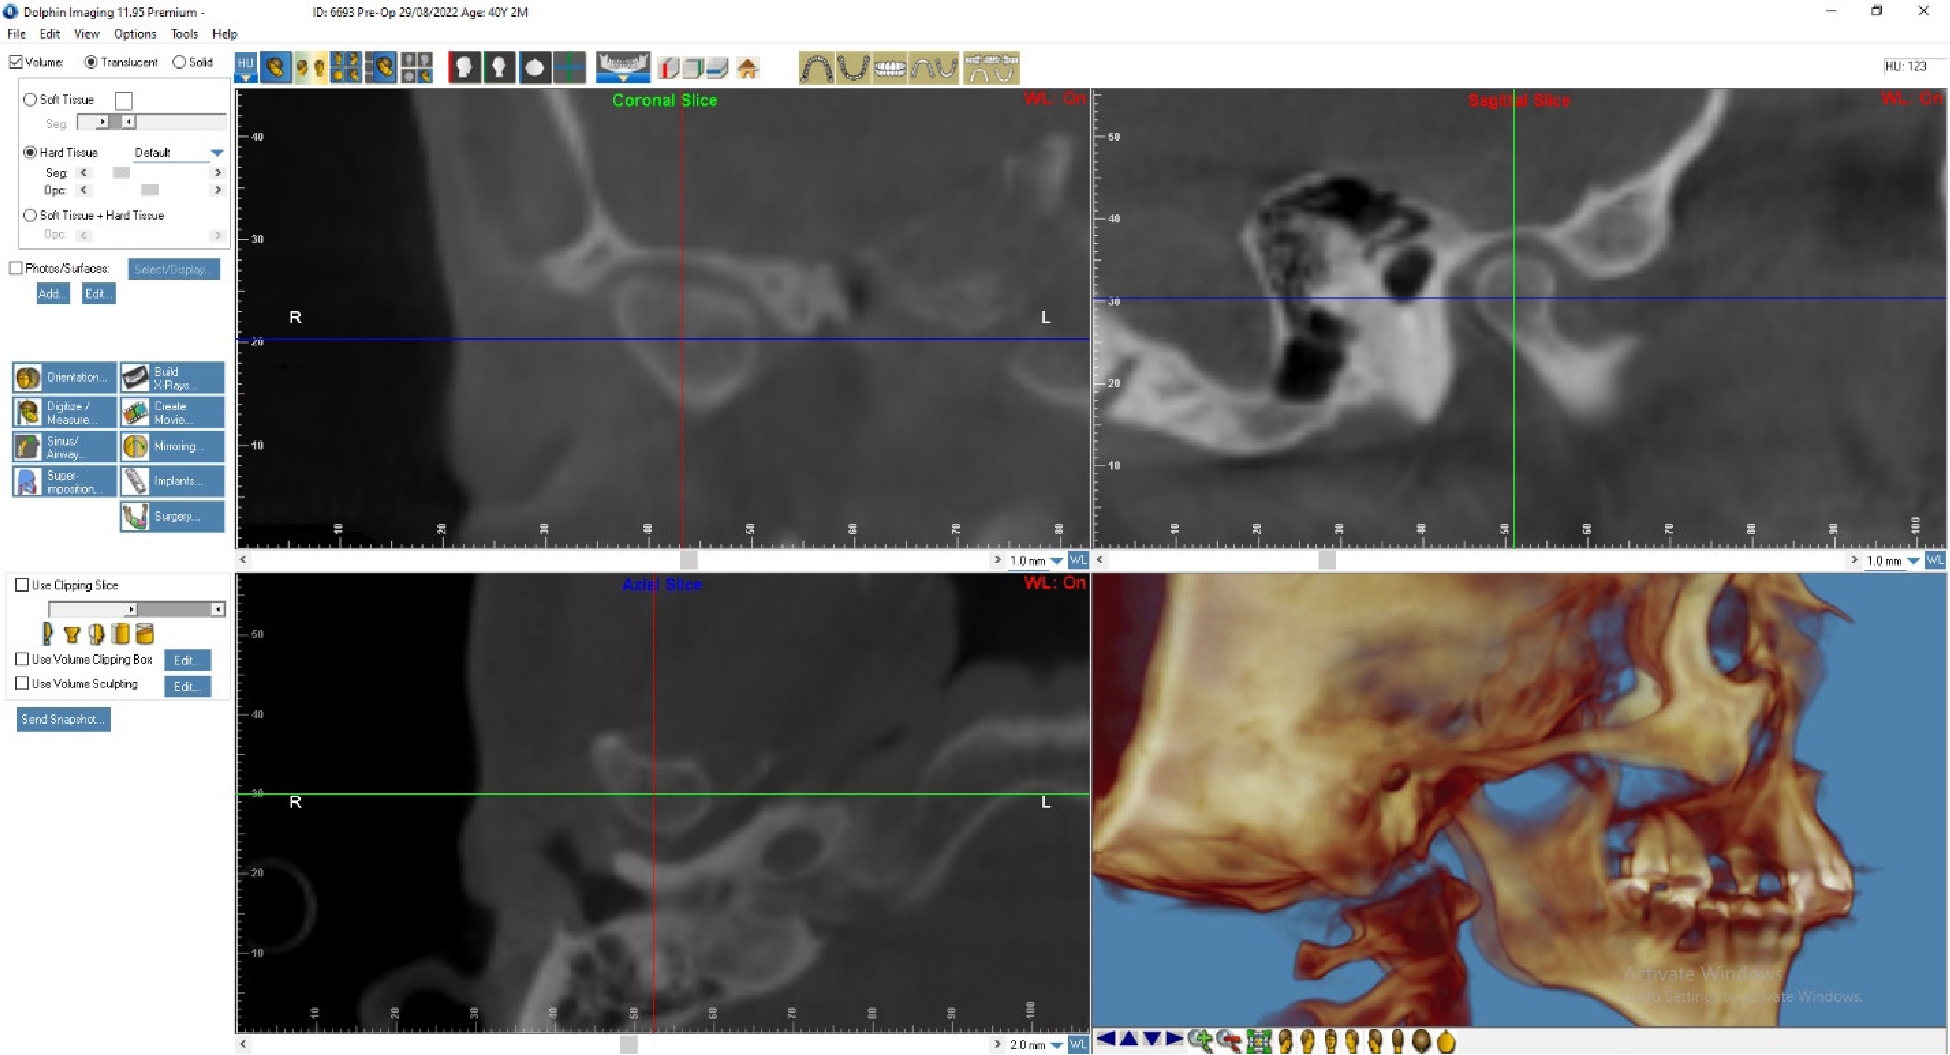

По данным МРТ ВНЧС спустя 2 года после начала лечения отмечается устранение вентро-латеральной дислокации суставного диска в положении привычной окклюзии. Также устранен синовит, увеличился объем движения в суставе (рис. 5). Как видно из рис. 4 и 5, по данным КТ ВНЧС спустя 2 года после начала лечения отмечается ремоделирование головки нижней челюсти. Клинически увеличилось открывание рта до 38 мм.

Рис. 4. Пациент Д., 38 лет. КТ ВНЧС до начала лечения

Рис. 5. Пациент Д., 40 лет. КТ ВНЧС спустя 2 года после начала лечения